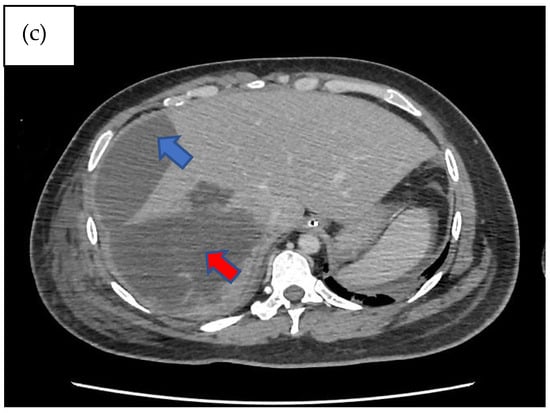

Figure 1.

Computed tomography scan of the abdomen non-contrasted phase showing heterogenous areas consisting of hematoma and laceration at segments V, VI, VII, and VIII extending down to the subhepatic region (red arrow). Inferiorly, it extends down to the hepatic flexure, just lateral to the right pararenal space. Another subcapsular collection was seen adjacent to right liver lobe (blue arrow): (a) coronal view, (b) sagittal view, and (c) axial view, with findings as aforementioned.

Imaging remains the gold standard for diagnosing bilomas, with ultrasound (US) often being the initial imaging modality used. Bilomas typically appear as well-defined hypoechoic fluid collections within the abdomen that vary in size and shape, ranging from small localized areas to larger, more extensive masses. It also has the capability of detecting the content within the biloma by showing a variety of findings ranging from well-defined collections in the liver parenchyma to extensive fluid collections across the abdomen [8]. Notably, US findings show heavily loculated bilomas are often linked to infection [9]. CT imaging can help identify the overall structure of the biloma, delineating clear margins that can be either encapsulated or non-encapsulated [10]. While CT imaging offers a more intricate view of bilomas, it lacks the capability to conclusively distinguish among various potential diagnoses, including seroma, abscess, lymphocele, liver cyst, hematoma, and pseudocyst [11]. Consequently, additional imaging modalities such as magnetic resonance (MR) imaging or hepatobiliary cholescintigraphy may be necessary to help validate the diagnosis. Direct sampling of the biloma together with these imaging techniques will also help with the diagnosis [10]. In T1-weighted images, bilomas will display low signal intensity, whereas in T2-weighted images, high signal intensity is seen [12]. Furthermore, MR imaging can help to define the characteristics of a biloma. While contrast infrequently penetrates the biloma, rim enhancement and septations occasionally occur due to reactive inflammation and infection [12]. Hepatobiliary cholescintigraphy serves as a highly efficient non-invasive imaging technique for diagnosing and strategizing treatment for bilomas by utilizing a radiotracer known as Tc-99m iminodiacetic acid, which is commonly referred to as hepatobiliary iminodiacetic acid (HIDA) imaging [10,13]. HIDA imaging exhibits a high level of sensitivity in detecting bile leaks [13]. Nonetheless, it lacks the ability to offer detailed imaging of the surrounding anatomical structures. Single positron emission computed tomography (SPECT) is another imaging technique that has the ability to furnish more intricate imaging of potential leak locations, proving particularly valuable in planning percutaneous image-guided drains [10]. Endoscopic retrograde cholangiopancreatography (ERCP) and percutaneous transhepatic cholangiogram (PTC) can be considered not only for diagnostic tests but also may offer some degree of intervention either percutaneously or endoscopically [13]. Other minimally invasive investigations available are CT-guided sampling technique and US-guided sampling technique. However, these techniques require laboratory assistance to analyse the sample collected [10]. In our case, CT imaging was sufficient to give us the information we need. The initial CT imaging (Figure 1) revealed a rim-enhancing lesion surrounding the biloma, suggesting a potential infective biloma. However, we did not perform a biopsy and or staining hepatic tissue during the hemi-hepatectomy to definitely confirm that Rhodotorula mucilaginosa originated from the biloma itself. This limitation underscores a key aspect of our study, highlighting the need for further investigations to establish a direct link between the presence of Rhodotorula mucilaginosa and the biloma. MR imaging was not performed in this patient which shows another limitation in this case. MR imaging might indicate presence of septations within the biloma and this might be the reason why percutaneous drainage failed in this patient.